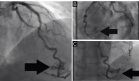

Se colocó una sonda uretral para derivación urinaria y se solicitó cistografía por TC, la cual evidenció una solución de continuidad en la pared posterolateral izquierda de la vejiga, con dimensiones aproximadas de 14x13 mm, permitiendo la extravasación de contraste en la cavidad peritoneal (uroperitoneo).

Durante la cistoscopia, se observó una fístula de bordes irregulares de aproximadamente 2 cm de diámetro en la cara posterolateral izquierda de la vejiga.

Para el abordaje laparoscópico, se emplearon cuatro trócares: uno umbilical de 12 mm, dos de 12 mm en ambas fosas ilíacas a nivel de la línea medioclavicular y un trócar accesorio de 5 mm en la fosa ilíaca derecha. Durante el procedimiento, se confirmó la presencia de orina en la cavidad peritoneal y un defecto irregular en la pared posterolateral izquierda de la vejiga.